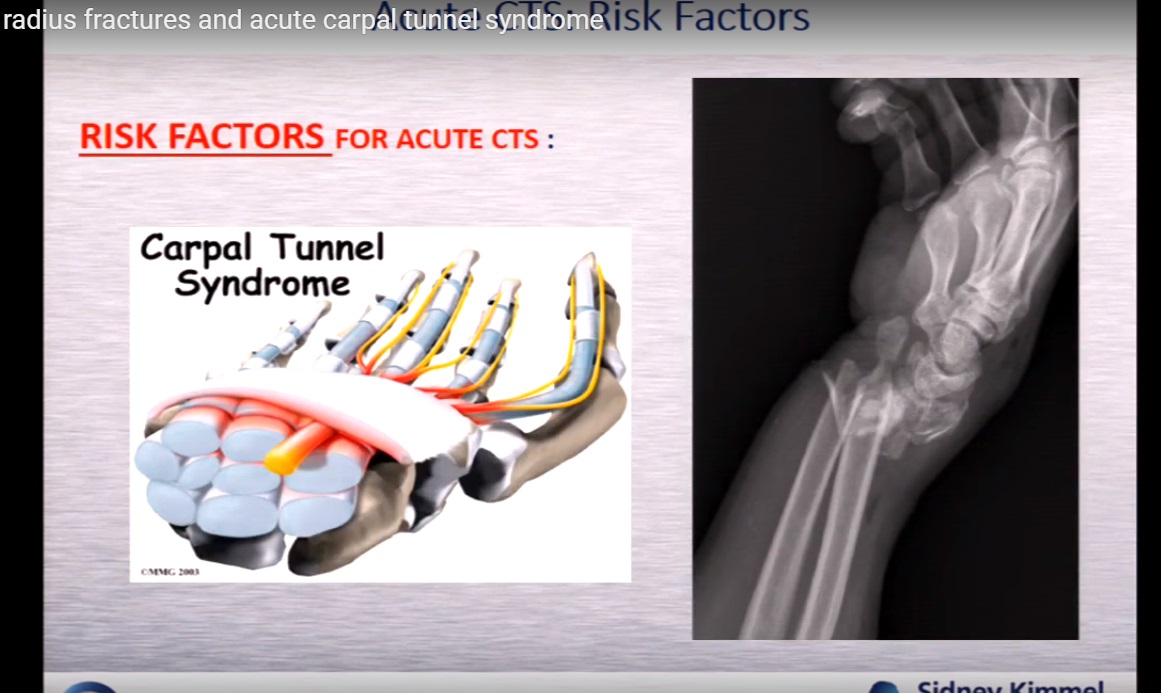

健康・医学 Distal Radius Fractures and Carpal Distal Radius Fractures and Acute Carpal Tunnel Syndromeの詳細情報

Distal Radius Fractures and Acute Carpal Tunnel Syndrome。Complex Regional Pain Syndrome after Distal Radius Fracture。Distal Radius fractures and acute Carpal tunnel syndrome。Acute Carpal Tunnel Syndrome in Pediatric Distal Radius。Distal Radius Fractures and Carpal Instabilities: FESSH IFSSH 2019 Instructional Book (English Edition)新品¥18,560Francisco del Pinal | 2019/6/24